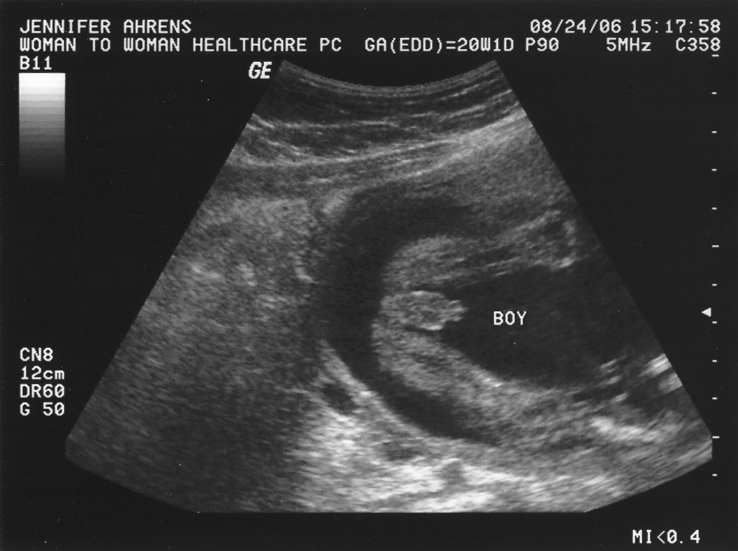

Важный этап: развитие малыша на 20-й неделе беременности

Раздел: Снимки-откровения